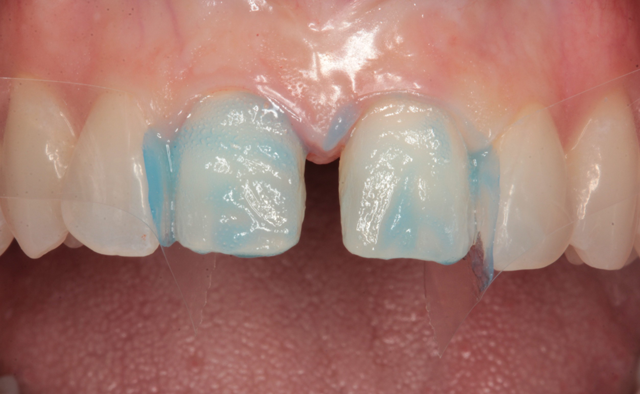

At the delivery appointment, the provisional veneers were removed and the new laminate veneers were tried in using Calibra try in paste (Dentsply/Sirona). The patient was asked to look in a mirror and she approved the new veneers. The veneers were removed and thoroughly cleaned with water spray from an air/water syringe and dried with oil-free air. A silane primer (Calibra Silane Coupling Agent, Dentsply/Sirona) was used to treat the etched intaglio surfaces (Fig. 9), allowed to dwell for twenty seconds and air dried.

Fig. 9 Fig. 10

Celluloid strips were placed distal to both central incisors to protect the adjacent teeth. Phosphoric acid edging gel (Calibra, Dentsply/Sirona) was placed on the prepared enamel surfaces (Fig. 10), thoroughly rinsed after ten seconds (Fig. 11) and air dried (Fig. 12).